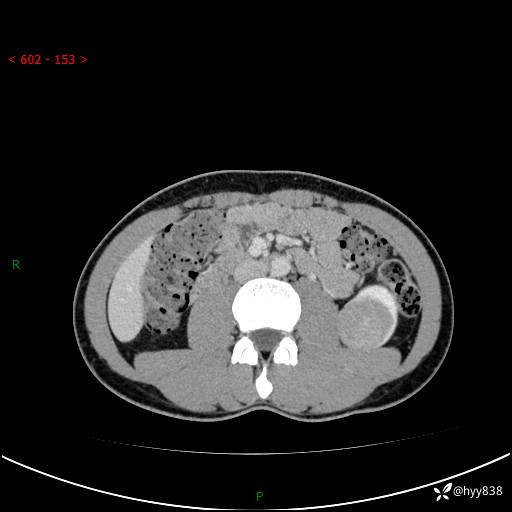

现病史:患者昨日中午进食后出现明显腹痛,腹泻,在我院急诊科行补液及对症治疗,双肾输尿管彩超提示左肾占位(5.2*4.3cm),平素无明显腰痛,无再发肉眼血尿等情况,现为求处理左肾占位,遂来我院,门诊以左肾占位收治入院。 患者起病以来,精神、食欲、睡眠尚可,大便可,小便如上,体力体重无明显下降。

双肾CT平扫+增强(三期)